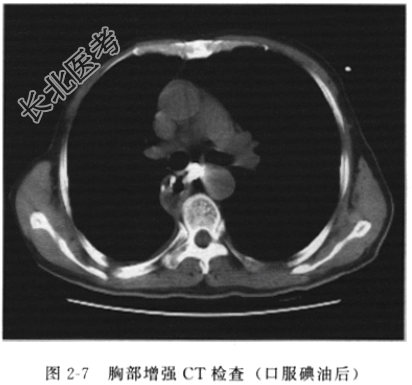

- [材料题] 患者女性,62岁,食管鳞癌术后放疗后8个月余,胸背痛1个月余,无咳嗽、咳痰,无胸闷、心悸等不适。患者既往已做过食管癌根治术,术后行放疗。查体:体温37.6℃,全身浅表淋巴结未扪及,心、肺、腹部查体无明显异常。门诊抽血常规检查:白细胞12×10/L,中性粒细胞百分比88%。心电图检查无明显异常。门诊以“食管癌术后放疗后复发?”收入院。入院后胸部增强CT检查(图2-7):食管癌术后放疗后复查,食管上段管壁可见金属影,为术后改变,胸廓入口食管管壁增厚,最厚处约18mm×16mm,食管腔狭窄,内可见高密度营养管影,增强扫描见增厚食管壁轻度强化;气管分叉下方纵隔内可见小片状高密度影。诊断为食管癌术后放疗后复发:①胸廓入口处食管壁增粗,符合食管癌术后复发;②食管纵隔瘘,纵隔内碘剂沉积。